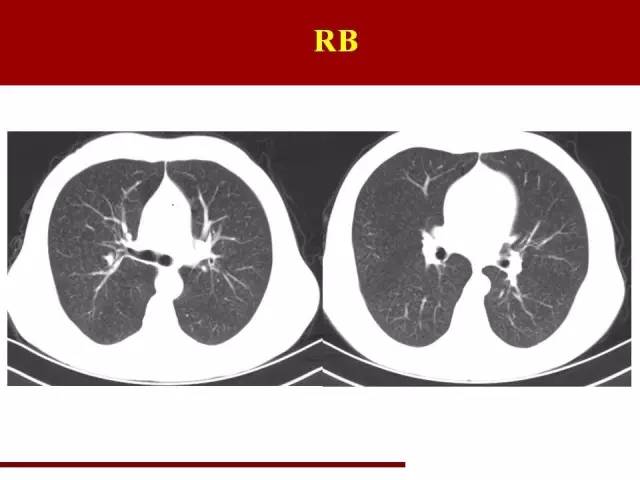

第三类是吸烟相关性间质性肺炎

吸烟导致连续性肺损害包括呼吸性细支气管炎

呼吸性细支气管炎间质性肺病 DIP,是同一损害的不同阶段

那么咱们看看处于中间状态的呼吸性细支气管炎间质性肺病应该是比较少见的,对吧,图片来自文献

这个是呼吸性细支气管炎,大家肯定经常见,但是往往不是视而不见就是误诊其他疾病

特点是双肺弥漫小叶中央型磨玻璃结节,边缘模糊,非常浅淡,中上肺野分布为著

RB通常需要和早期尘肺鉴别

因为从事粉尘作业的工人多数都吸烟,那么遇到这样的患者是诊断RB还是尘肺意义就完全不一样

在实际工作中经常有这样的病例出现

尘肺结节既有小叶中央型结节也有淋巴道来源结节,所以分布不一样

另外结节边缘相对清楚,密度较RB高

RB-ILD处于中间状态,时间短,所以不一定能抓住典型图像

表现为RB的基础上出现空气潴留,是其特点,但是不容易诊断